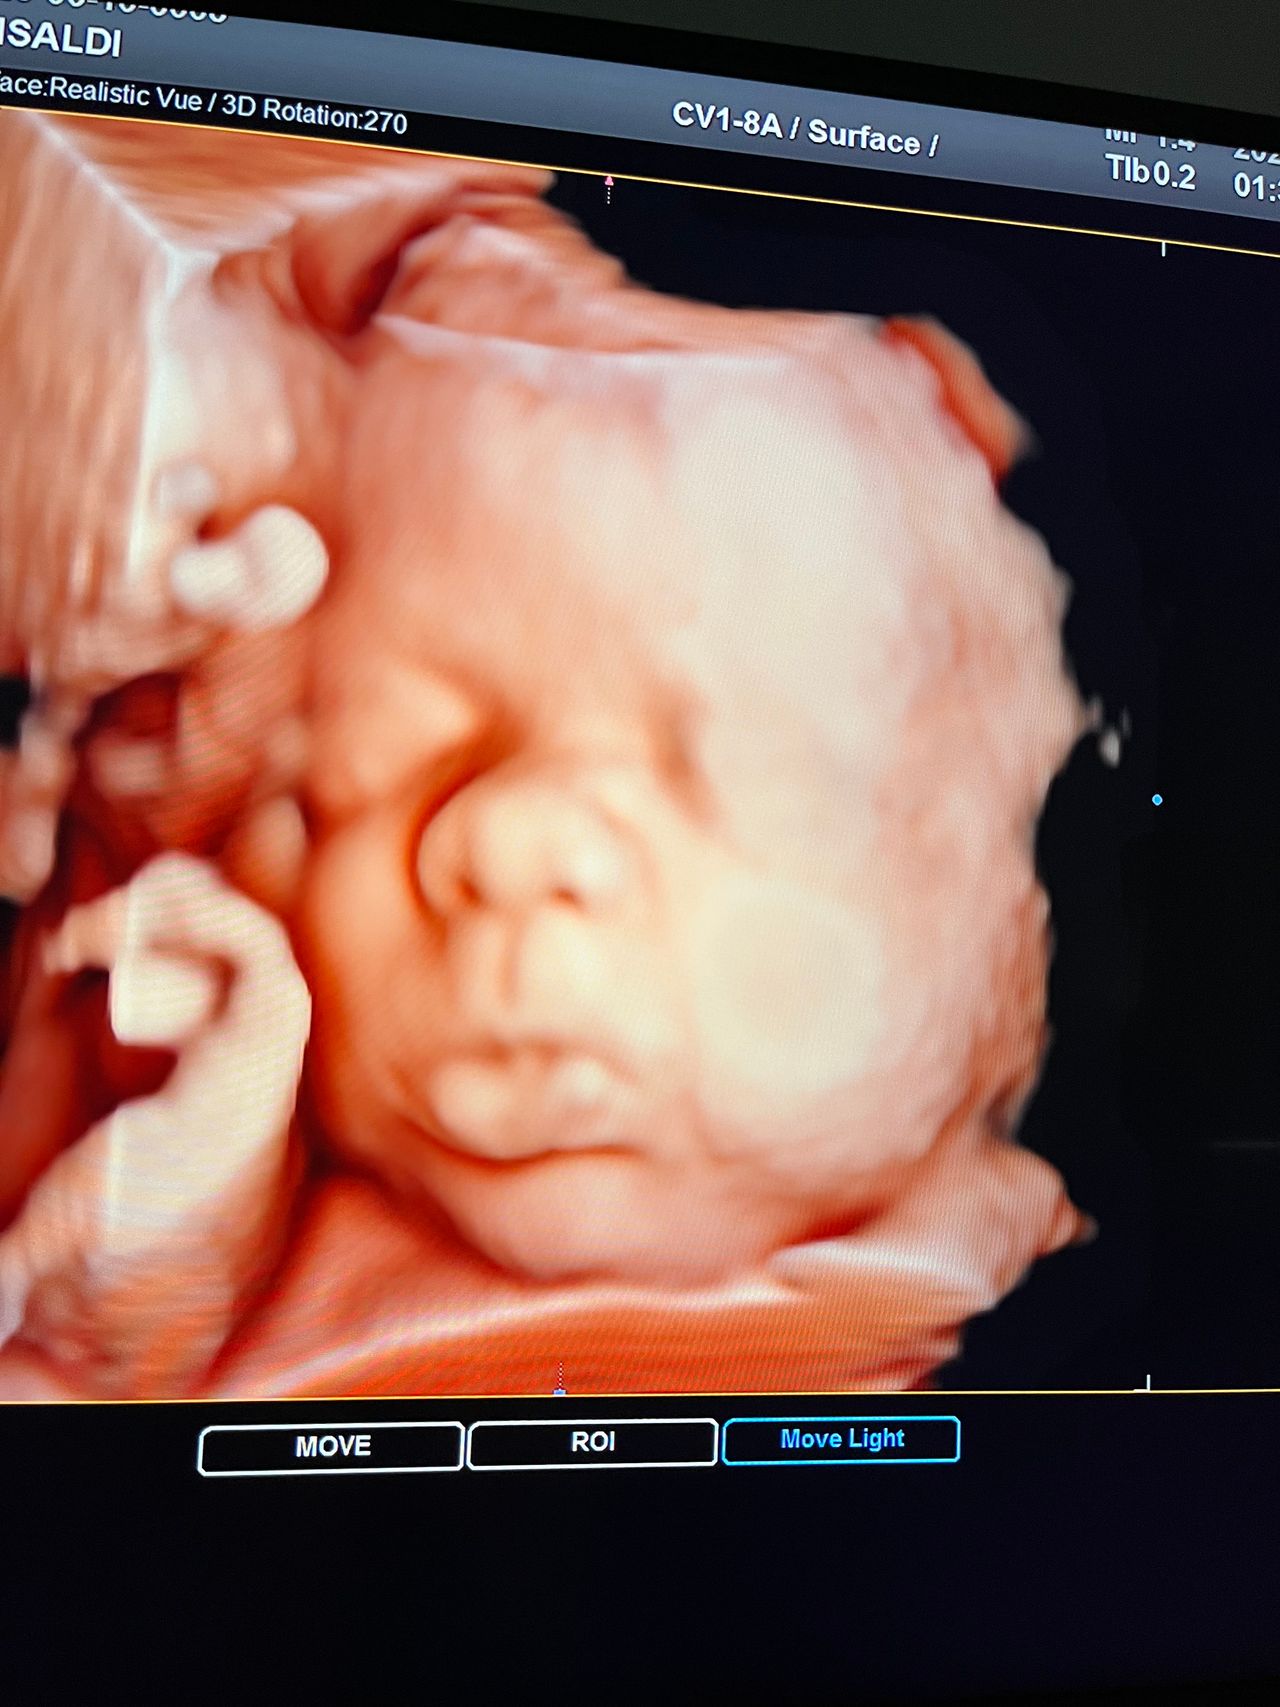

Attualmente lavoro come Dirigente medico nella SC di Ostetricia e Ginecologia dell'Ospedale Michele e Pietro Ferrero di Verduno, mi occupo prevalentemente di screening prenatale, ecografia ostetrica del I trimestre( misurazione translucenza nucale,NT), ecografia morfologica del II trimestre, ambulatorio pregresso taglio cesareo, ecografia ostetrica 3D. Seguo le gravidanze fisiologiche e quelle ad alto rischio , presto servizio in sala parto. Eseguo visite ginecologiche di I-II livello in regime ambulatoriale, counseling contraccettivo ed eventuale prescrizione pillola, inserimento spirale (IUD), dispositivo sottocutaneo (Nexplanon).

Foto e video